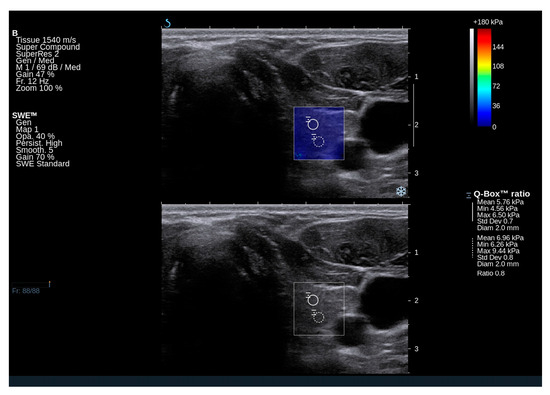

2.3. Elastography Results

4.2. Thyroid Ultrasound and Shear Wave Elastography (SWE)

| Right lobe Qbox mean (kPa) | 17.2 (11.9–20.9) | |

| Right lobe Qbox min (kPa) | 11.3 (6.8–13.3) | |

| Right lobe Qbox max (kPa) | 25.4 (18.8–31.5) | |

| Right SD | 3.5 (2.7–4.5) | |

| Left lobe Qbox mean (kPa) | 14.9 (11.3–21.5) | |

| Left lobe Qbox min (kPa) | 8.7 (5.3–12.5) | |

| Left lobe Qbox max (kPa) | 22.9 (17.3–29.6) | |

| Left SD | 3.2 (2.1–4.0) | |